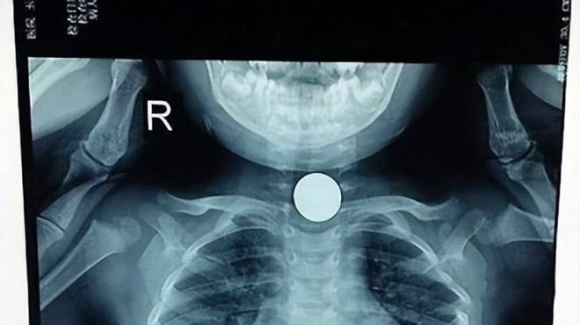

Rất nhiều bác sĩ y tá tích cực cấp cứu cho Tiểu Ngọc, nhưng cuối cùng lại đưa ra kết luận "quá muộn", kỳ tích đã không xuất hiện và tim cô bé đã ngừng đập. Bác sĩ tiến hành kiểm tra toàn diện thì phát hiện một viên kẹo có hình tròn và cứng đang mắc kẹt trong đường thở của Tiểu Ngọc, khiến đứa trẻ bị ngạt thở. Đây chính là nguyên nhân dẫn đến bi kịch này.

Ảnh minh hoạ